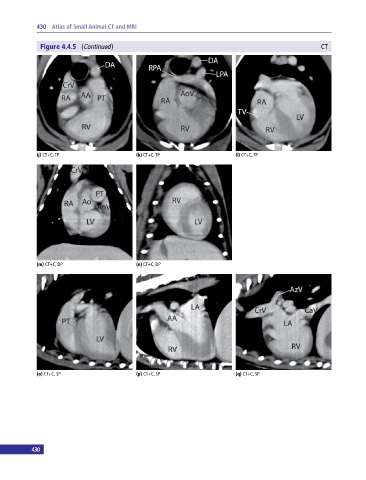

Figure 4.4.5  (Continued  )                                                                  CT

(j) CT+C, TP                     (k) CT+C, TP                     (l) CT+C, TP

(m) CT+C, DP                     (n) CT+C, DP

(o) CT+C, SP                     (p) CT+C, SP                     (q) CT+C, SP